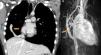

A nine-year-old girl was referred to the pediatric cardiology department for a cardiac murmur and Turner syndrome. She was asymptomatic and presented an ejection systolic murmur at the left sternal border. The electrocardiogram (ECG) showed right bundle branch block and the echocardiogram showed no intracardiac shunts, right ventricular dilatation with abnormal motion of the ventricular septum, and normal biventricular function. Cardiac catheterization revealed a normal heart with Qp/Qs 1:1. She continued to be followed in the pediatric cardiology clinic. At the age of 13 years she still presented right ventricular dilatation with an intact interatrial septum. MRI (Figure 2A and B) showed a partial anomalous pulmonary venous connection to the brachiocephalic vein, intact interatrial septum, right ventricular dilatation and Qp/Qs 1.6:1. She underwent cardiac surgery with a good outcome. This case highlights the potential role of MRI in these anomalies and is a reminder that although it is still the gold standard, cardiac catheterization when performed incorrectly may give inaccurate information. One of the key points is to take venous blood samples at various levels in order to obtain precise results.